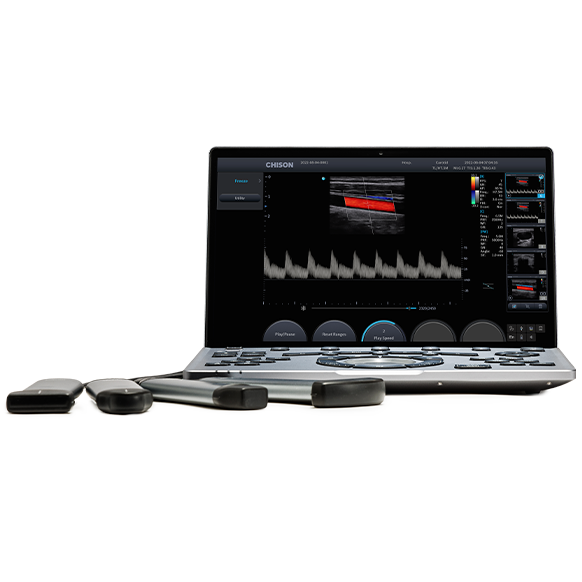

SONOAIR 30 VET – інноваційний портативний ультразвуковий апарат CHISON, що поєднує в собі якість зображення високої чіткості та інтелектуальні функції, щоб допомогти ветеринарам досягти швидкої та надійної діагностики.

SonoAir 30 VET пропонує комплексне ультразвукове рішення зі зручним та інтуїтивно зрозумілим користуванням для щоденних обстежень на місці та виїзді до пацієнта. Апарат поєднує високу та чітку якість зображення, надзвичайно зручний інтерфейс та має унікальну ергономічність, що дозволяє спеціалісту працювати з задоволенням та легко і швидко ставити діагноз.

Найбільш інноваційний, найлегший і найтонший сенсорний портативний ультразвуковий апарат CHISON SonoAir 30 VET у вигляді ноутбуку відповідає сучасним запитам часу та поєднує в собі якість зображення високої чіткості та інтелектуальні функції, щоб допомогти лікарям досягти швидкої та надійної діагностики.

Технічні характеристики SonoAir 30 VET:

• 2,1 кг Надлегка вага (з акумулятором)

• 26 мм Товщина

• Чуйтливий сенсорний екран діагоналлю 14,1 дюйма з регульованим кутом 135 °

• Висока роздільна здатність 1920 *1080, забезпечує високу чіткість

• Легке підключення за допомогою максимум 4 портів

• 180+хв роботи на акумуляторі та 36год+ в режимі stand by

• Touch ID

• Металевий алюмінієвий корпус для тривалого використання